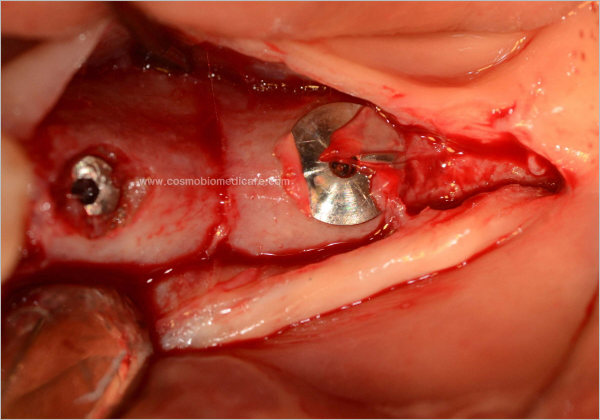

Clinical Cases

• Case1